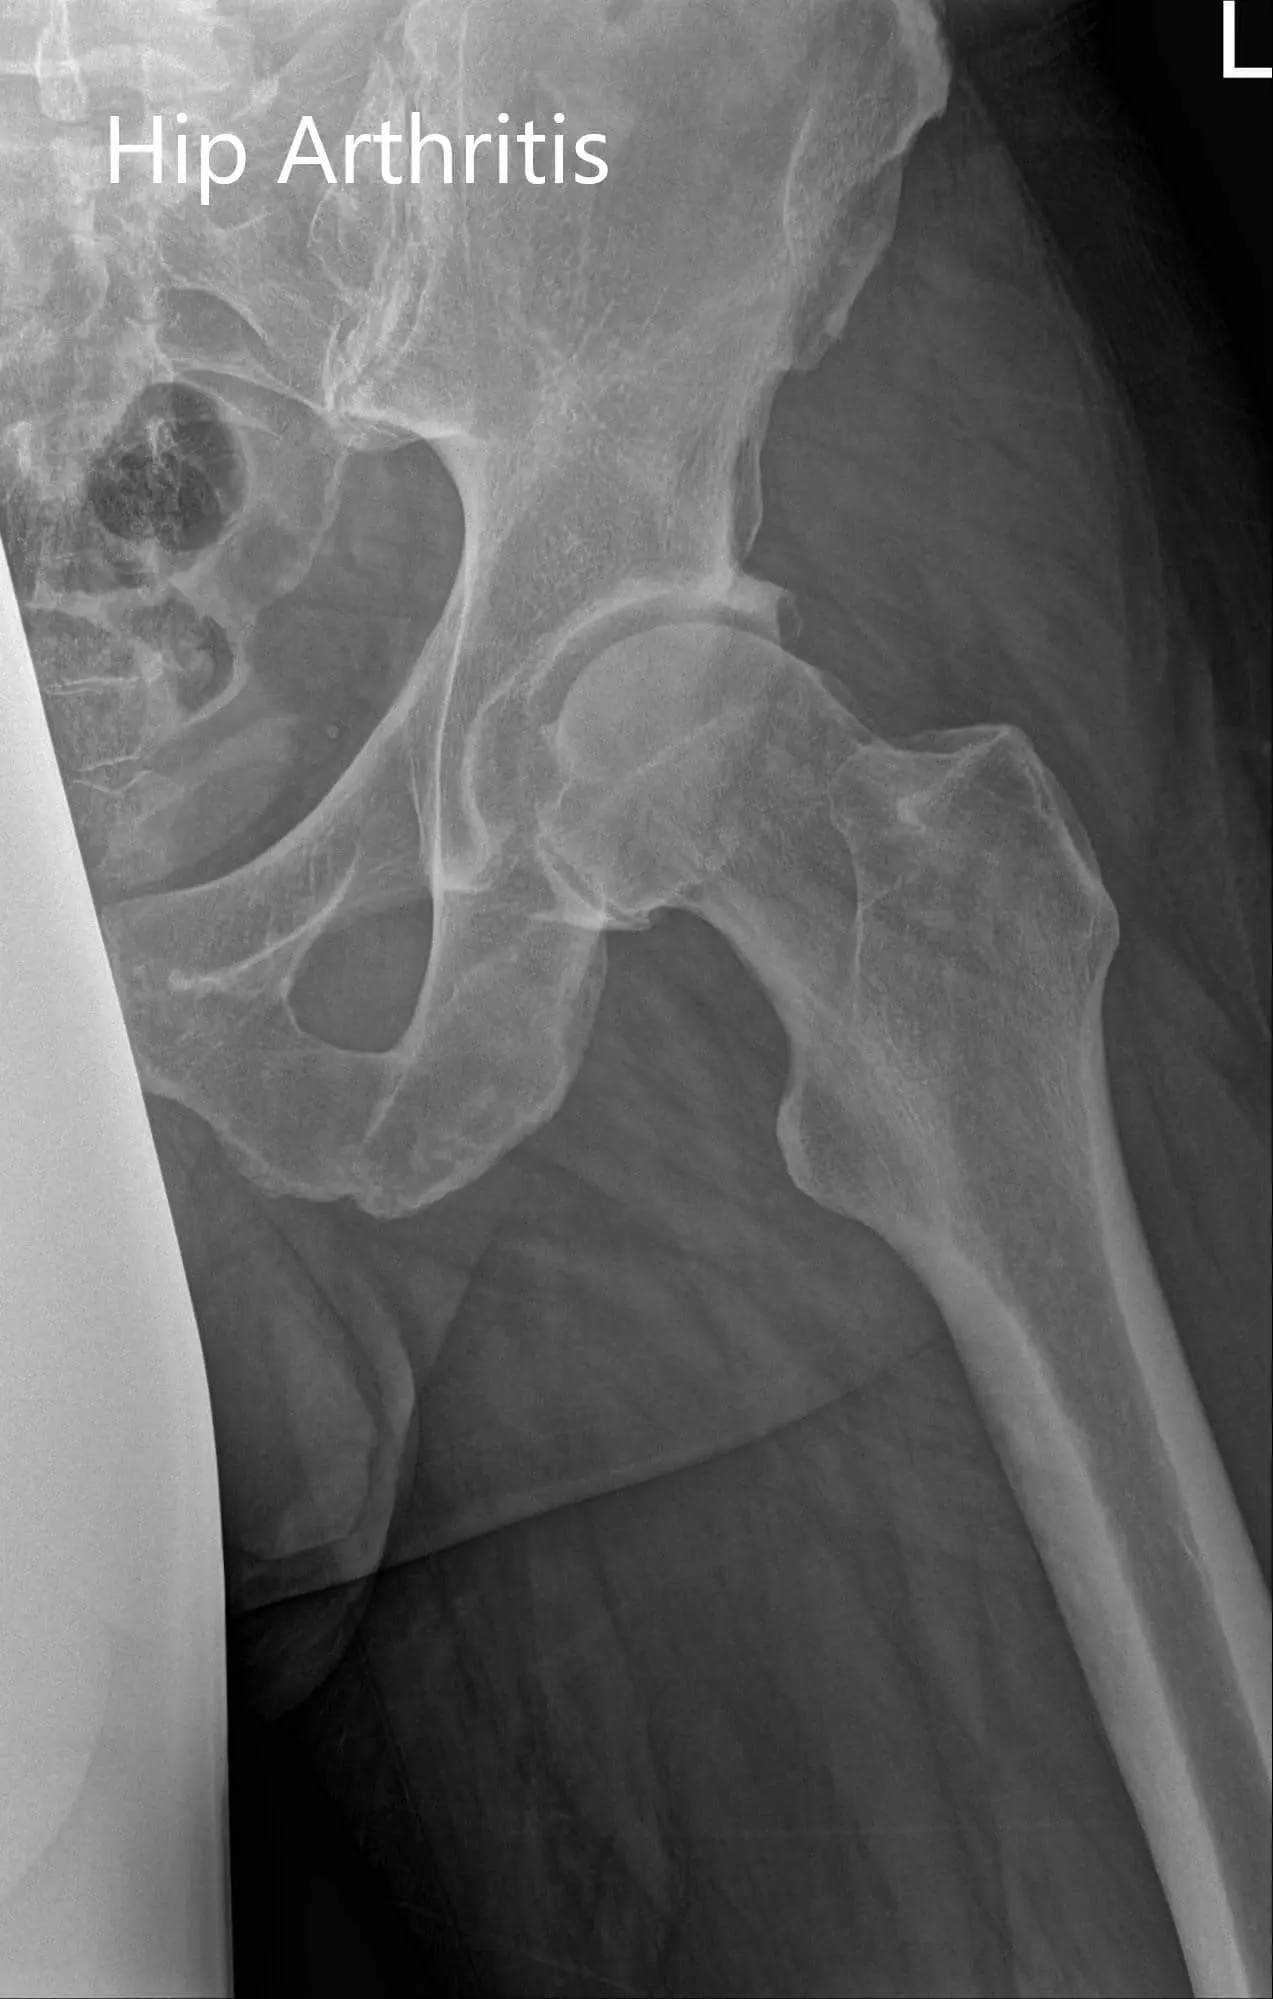

Her imaging studies revealed arthritis changes in both her hips. Considering her lifestyle limiting hip pain, she was advised to undergo bilateral hip total replacement. Risks, benefits, and alternatives were discussed with her as well with her husband at length. She agreed to go ahead with left hip replacement.

Preoperative X-ray of the pelvis AP view and the lateral view of the left hip.